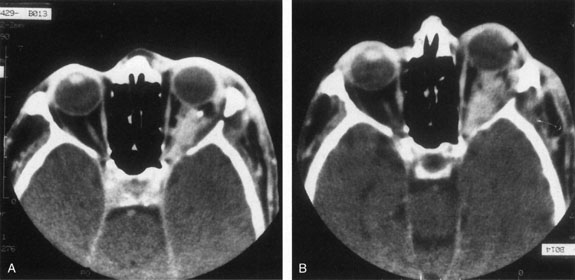

Contrast-enhanced CT of the orbits with direct and coronal cuts is the radiologic study of choice for these patients.45 A well-demarcated, encapsulated oval or rounded mass is revealed, which is typically intraconal in the lateral part of the middle third of the orbit (Fig. 5) but occasionally may extend to the extraconal space.42 Septa within the tumor may be apparent on high-resolution CT. The posterior pole of the globe frequently is indented by the rounded anterior margin of the tumor.42 The optic nerve typically is displaced rather than surrounded by the tumor. Subtle outward bowing of the lateral orbital wall or increase in orbital size may be present, consistent with a long-standing, slowly growing mass lesion.10,42 Enhancement with intravenous contrast occurs and may be homogeneous or inhomogeneous.10,45 Rarely, cavernous hemangiomas may occur as an intraosseous tumor within the orbital or facial bones.42,53–55 Although usually an isolated intraorbital lesion, multiple lesions in one orbit occurred in 8 of 164 (5%) patients of three combined large studies,10,42,45 and bilateral multiple cavernous hemangiomas also have been described.56 In contrast to patients with venous flow malformations in which phleboliths are common, phleboliths are rare in cavernous hemangiomas. Three large studies comprising 164 patients with cavernous hemangioma all reported that no calcification was detected within the tumor.10,42,45If the diagnosis is still unclear or if better definition of details and localization of the lesion is required, then MRI should be performed. Magnetic resonance imaging demonstrates nonspecific characteristics of a lesion isointense to muscle and gray matter on T1-weighted images and hyperintense on T2-weighted images (Fig. 6).57 The lesions show initial central patchy enhancement, which fills up homogeneously within 20 to 60 minutes.58 If ultrasonography is performed, B-scan ultrasonography shows a well-circumscribed mass with a sharply defined anterior acoustic border.23 A-scan ultrasonography shows high reflectivity of the echo signals resulting from the multiple blood-filled vascular channels, regular internal structure with a higher anterior and posterior spike marking the capsule, and moderate sound attenuation (angle of decrease of the echo spike within the lesion).24 Arteriography is not indicated.